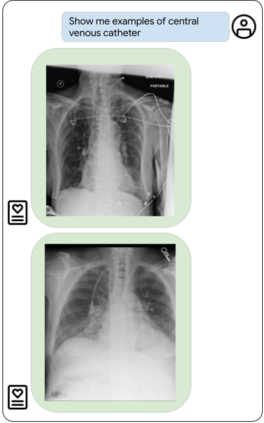

Our approach, which we call Embeddings for Language/Image-aligned X-Rays, or ELIXR, leverages a language-aligned image encoder combined or grafted onto a fixed LLM, PaLM 2, to perform a broad range of tasks. We train this lightweight adapter architecture using images paired with corresponding free-text radiology reports from the MIMIC-CXR dataset. ELIXR achieved state-of-the-art performance on zero-shot chest X-ray (CXR) classification (mean AUC of 0.850 across 13 findings), data-efficient CXR classification (mean AUCs of 0.893 and 0.898 across five findings (atelectasis, cardiomegaly, consolidation, pleural effusion, and pulmonary edema) for 1% (~2,200 images) and 10% (~22,000 images) training data), and semantic search (0.76 normalized discounted cumulative gain (NDCG) across nineteen queries, including perfect retrieval on twelve of them). Compared to existing data-efficient methods including supervised contrastive learning (SupCon), ELIXR required two orders of magnitude less data to reach similar performance. ELIXR also showed promise on CXR vision-language tasks, demonstrating overall accuracies of 58.7% and 62.5% on visual question answering and report quality assurance tasks, respectively. These results suggest that ELIXR is a robust and versatile approach to CXR AI.